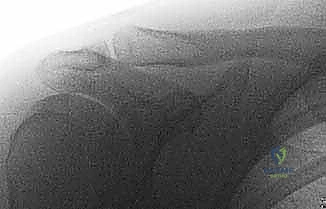

Standard shoulder radiographs are useful, but often overpenetrated, obscuring the AC joint.

* Zanca View: This is a game-changer. A 10- to 15-degree cephalic tilt view avoids superposition of the scapular spine, significantly improving visualization of the AC joint. It also helps identify any small fractures or loose bodies that might be missed on standard views.

FIG 1 • Zanca view of the acromioclavicular joint.

* Stress Radiographs: While some authors recommend standing views with 10-15 pounds of traction to distinguish injury grades, recent literature does not support their routine use as they often don't alter operative decision-making. However, a single AP view with both AC joints visible is invaluable for comparing to the contralateral side and assessing the degree of displacement, accounting for normal variants.